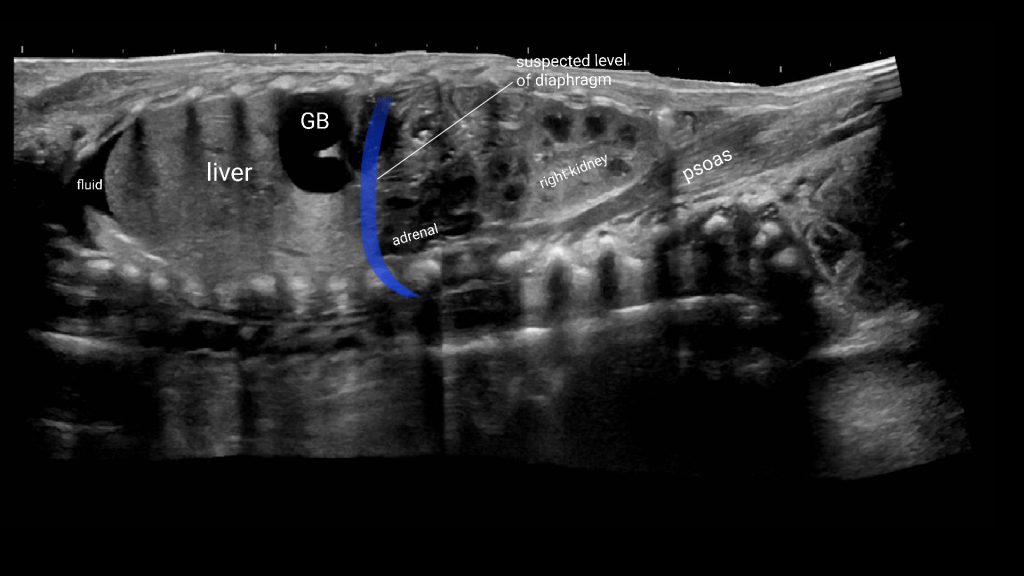

Diaphragmatic Hernia

Congenital diaphragmatic hernia is a defect or hole in the diaphragm that allows abdominal contents to enter the chest cavity. Most cases are diagnosed prenatally. Neonates typically present with respiratory distress acutely after birth. The lung on the affected side is usually hypoplastic.

Diapharagmatic hernias are usually classified by location.

- Location

- Posterolateral (Bochdalek)

- 80-90% of CDH

- 85% are left-sided, 10% right and 5% bilateral

- Anterior retrosternal or parasternal (Morgagni)

- 2% of all CDH

- Often asymptomatic in newborn period

Liver and gallbladder in right chest